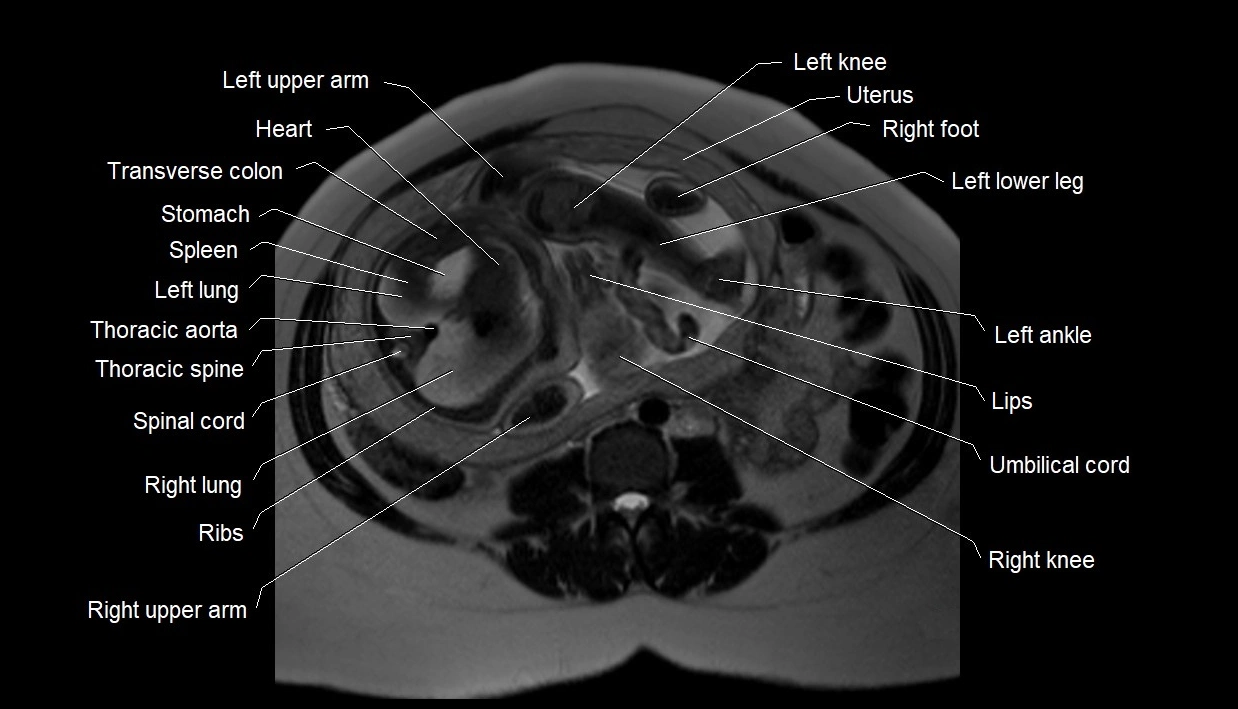

Relations

• Enclosed within the amniotic sac, bounded by the amnion and chorion

• Surrounds and cushions the developing fetus

• In continuity with maternal circulation through placental and transmembrane exchanges

MRI Appearance

T2 HASTE (T2 GRE):

• Amniotic fluid shows very bright hyperintense signal

• Provides natural contrast against fetus and placenta

• Small particles (vernix) may appear as scattered hypointense foci within bright fluid